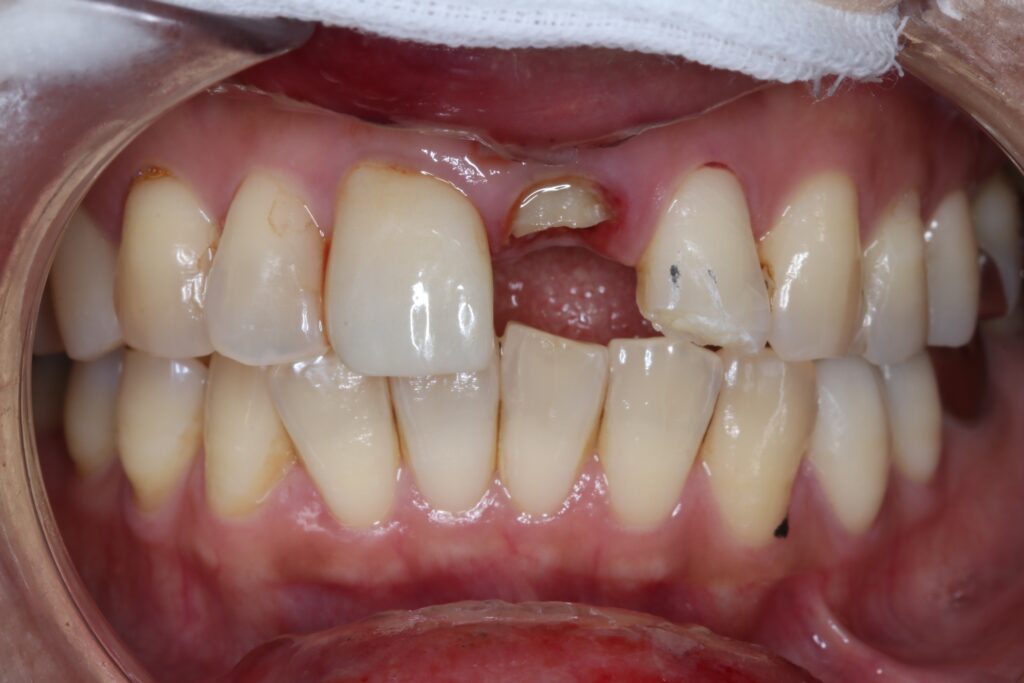

セラミック症例⑧

年齢40代女性

治療期間2ヶ月

治療内容セラミッククラウン

治療箇所左上1番

治療費用100,000円